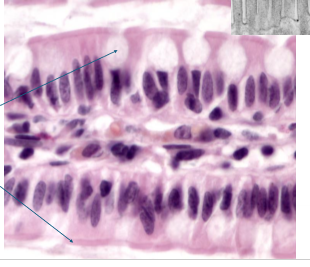

what is this?

PCCE

What is PCCE?

found in upper airway,s helps protect and move mucus

all cells attached to basement membrane, don’t all reach apical surface

lots of goblet cells

cilli on apical surface